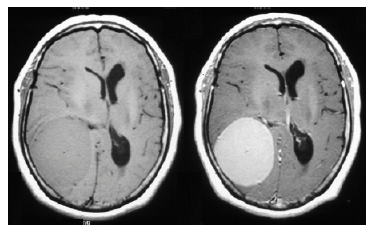

Uma paciente de 57 anos de idade, proveniente do interior de São Paulo, refere cefaleia holocraniana há cerca de quatro anos. Há três meses, houve uma piora da cefaleia, acompanhada de episódios de vômitos e dificuldade para caminhar. Ao exame físico, apresentava fundo de olho com edema de papila bilateral e hemiparesia no hemicorpo esquerdo.

Realizou investigação complementar com exames de ressonância magnética sem e com contraste, que evidenciaram as imagens abaixo.

RM T1 sem contraste RM T1 com contraste

Com base nesse caso hipotético, assinale a alternativa correta.